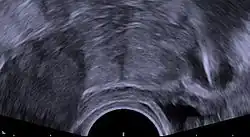

Transvaginal ultrasonography visualizing an IUD with copper in the optimal location within the uterus.

The absolute risk of ectopic pregnancy with IUD use is lower than with no contraception due to the dramatically decreased rate of pregnancy overall. However, when pregnancy does occur with a copper IUD in place, a higher percentage of those pregnancies are ectopic, from 3% to 6%, a two to sixfold increase. This corresponds to an absolute rate of ectopic pregnancy in copper IUD users of 0.2–0.4 per 1000 person-years, compared to 3 per 1000 person-years in the population using no contraception.[33][11][1]